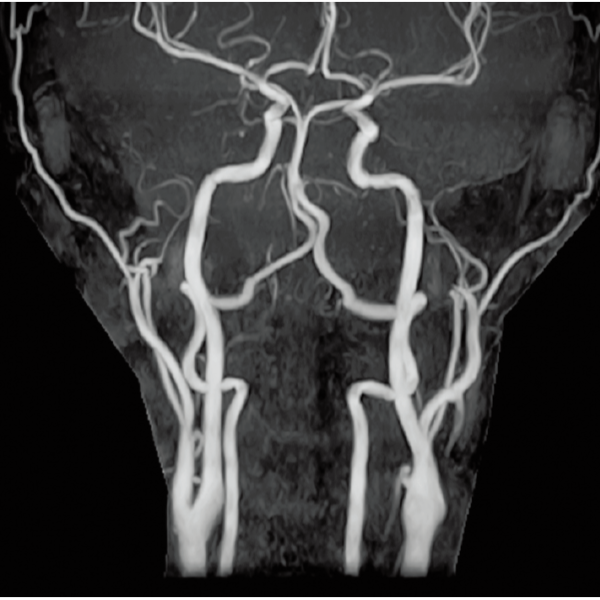

3DTOF MRA (MIP), 1:26